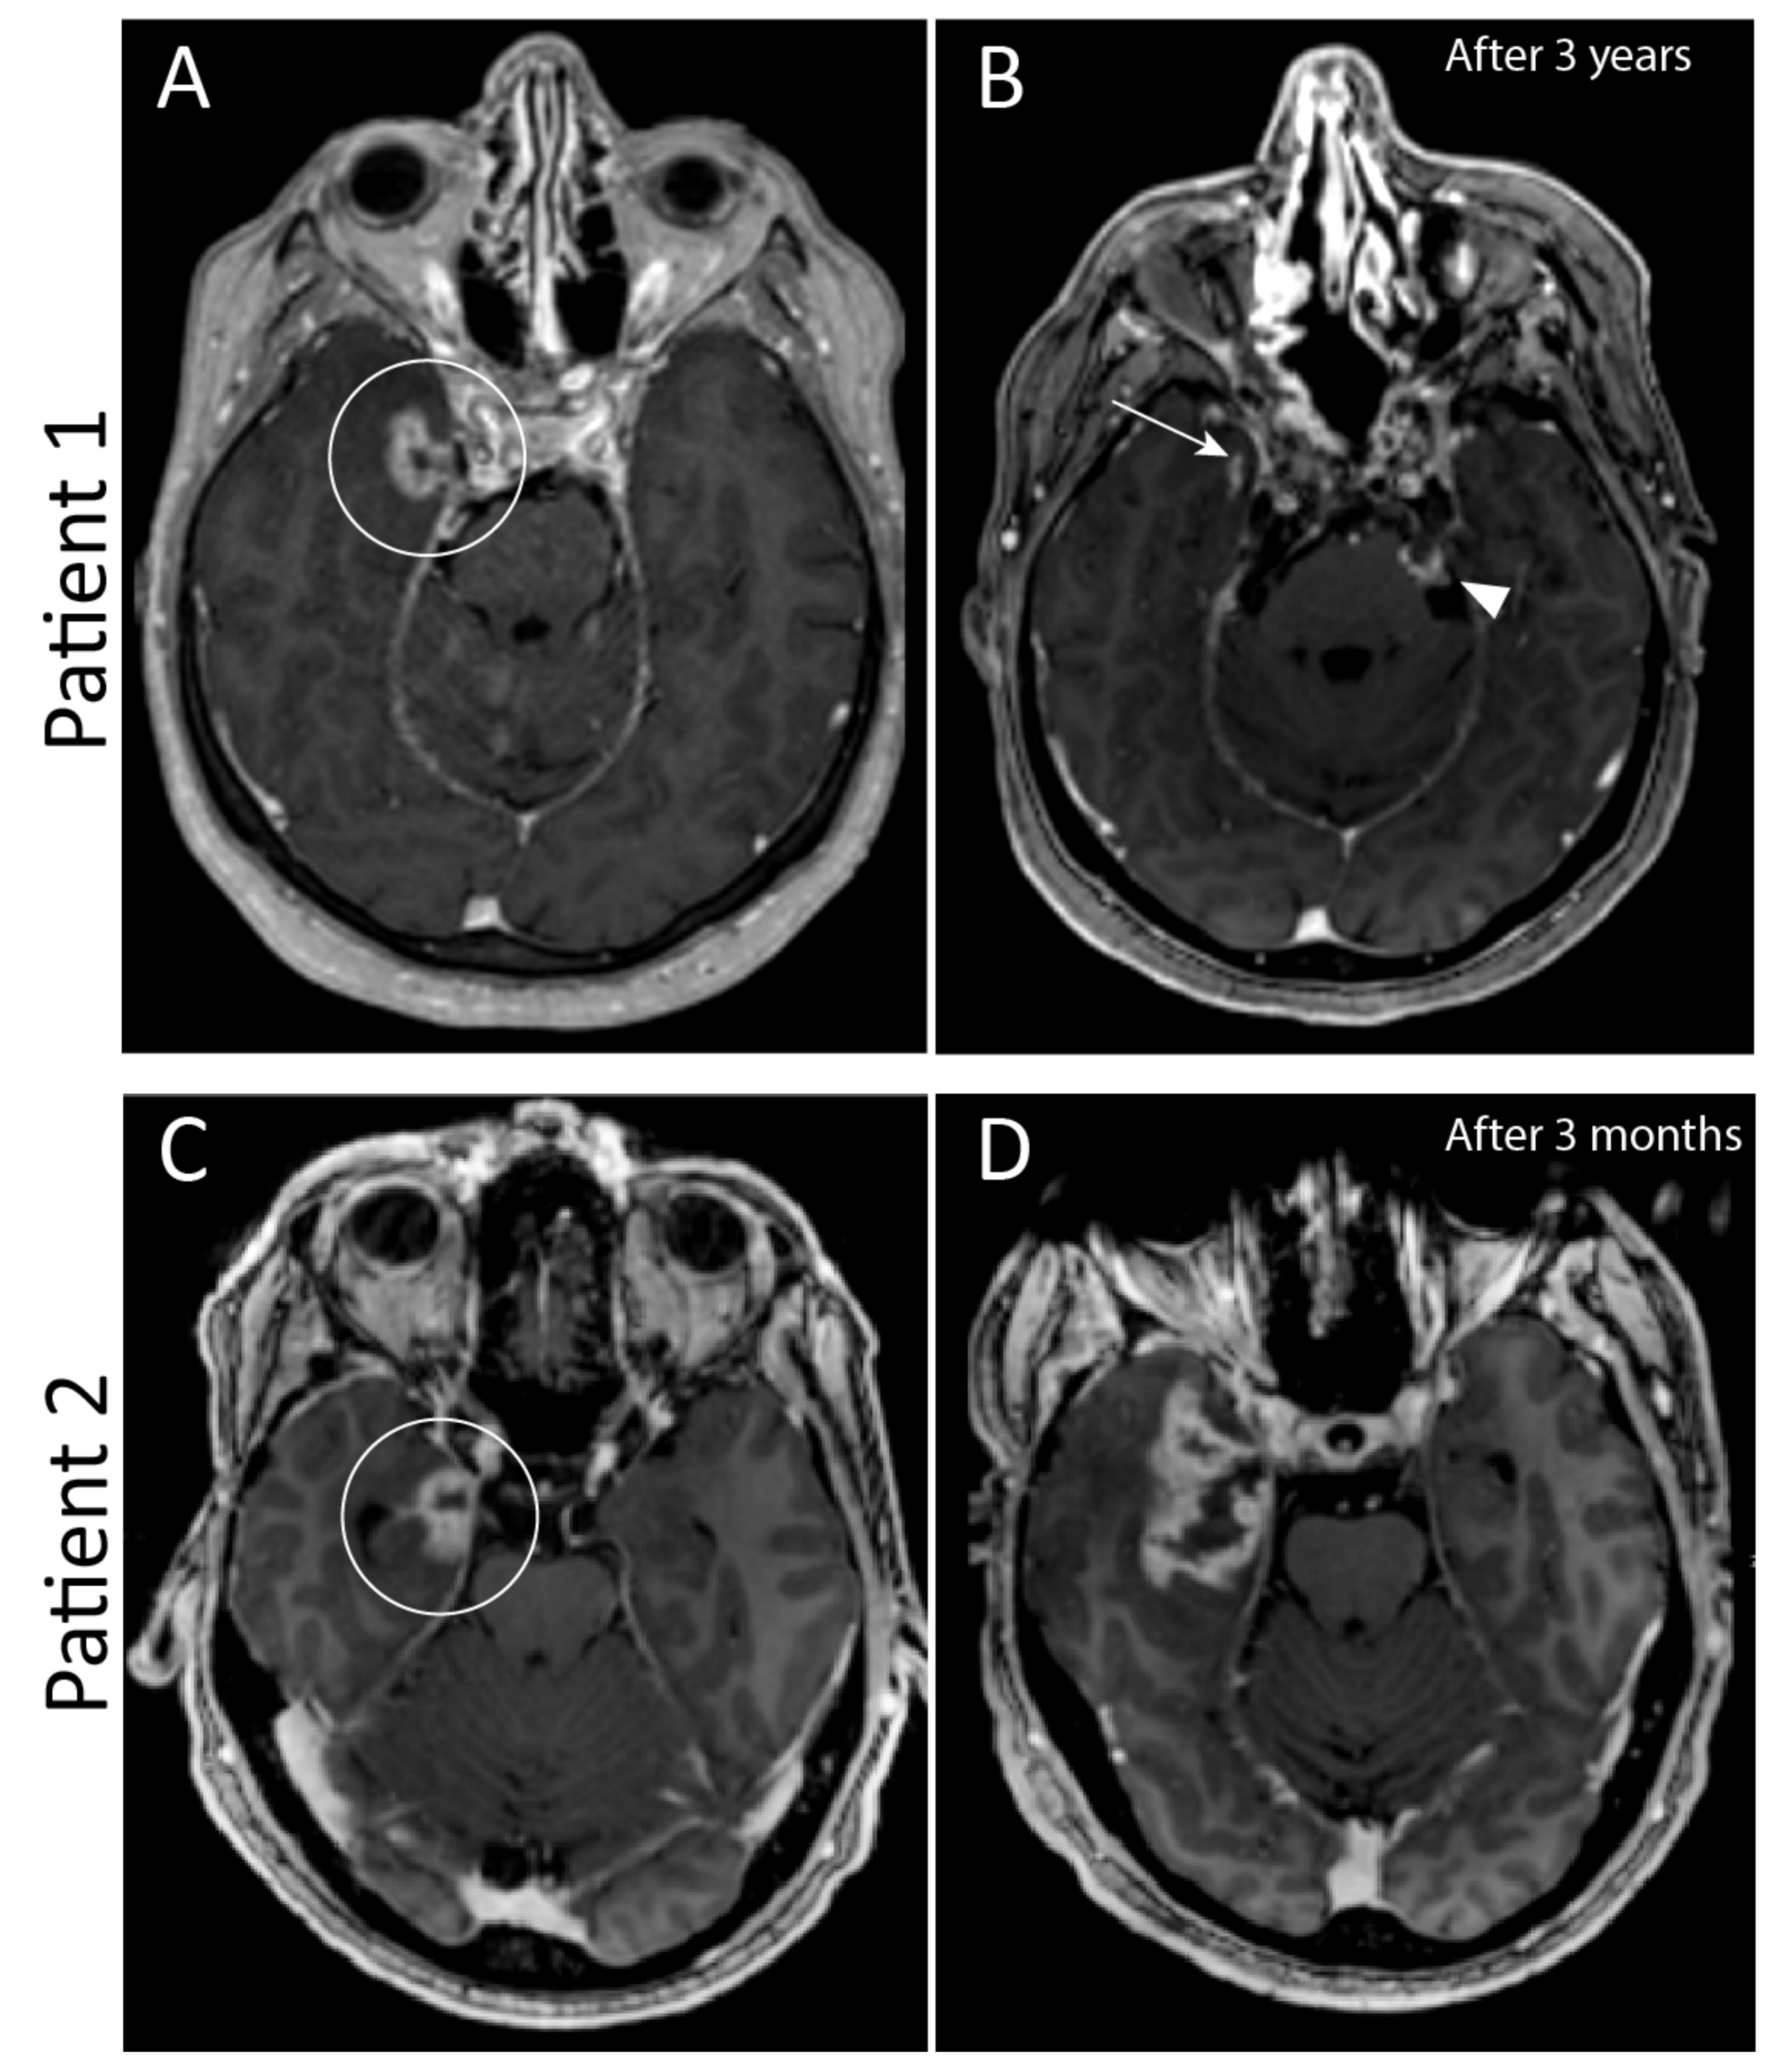

| 1 | Clivus |

| Proton | 2x Ala major os sphenoid 2x Cutaneous nodules | 9 | Surgery Photon radiotherapy (Linac) |

| 2 | Craniocervical junction |

| Proton/Photon | Paravertebral paramedian right Neuroforamen C4-C5 right | 7 | Surgery Proton therapy |